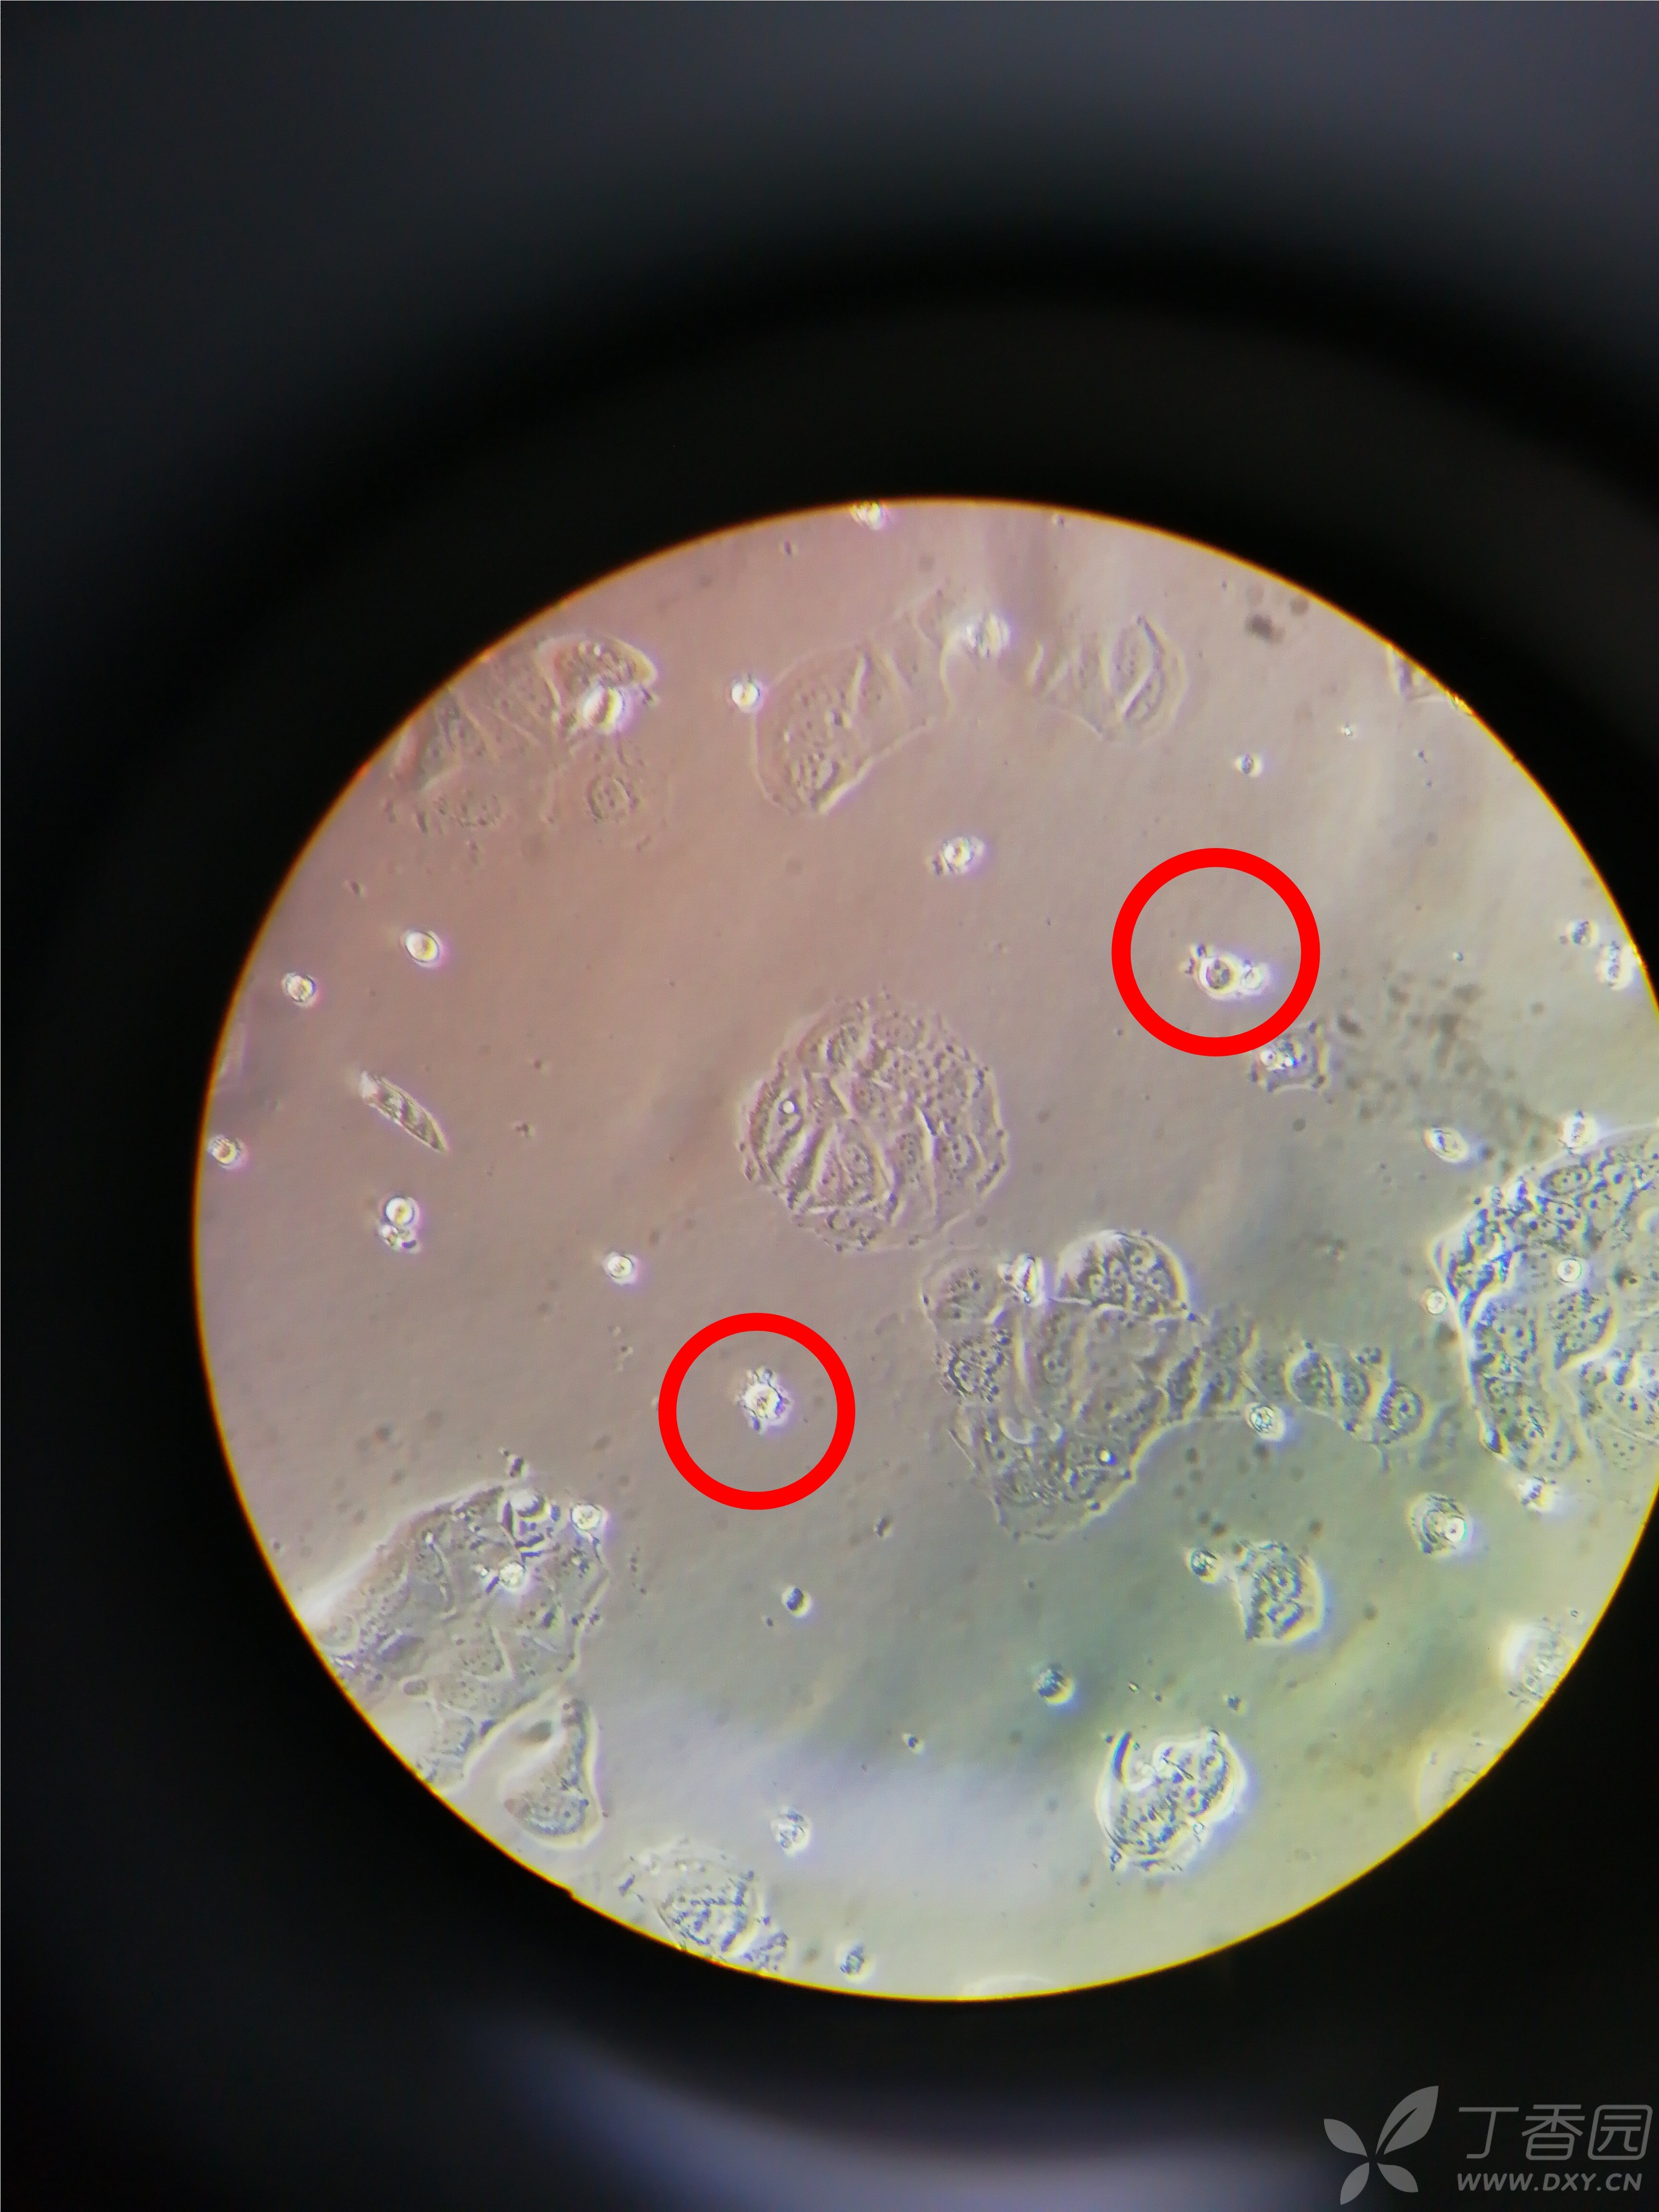

我的mcf-7人乳腺癌细胞形态正常不?

图片尺寸3456x4608

图片尺寸3457x4609